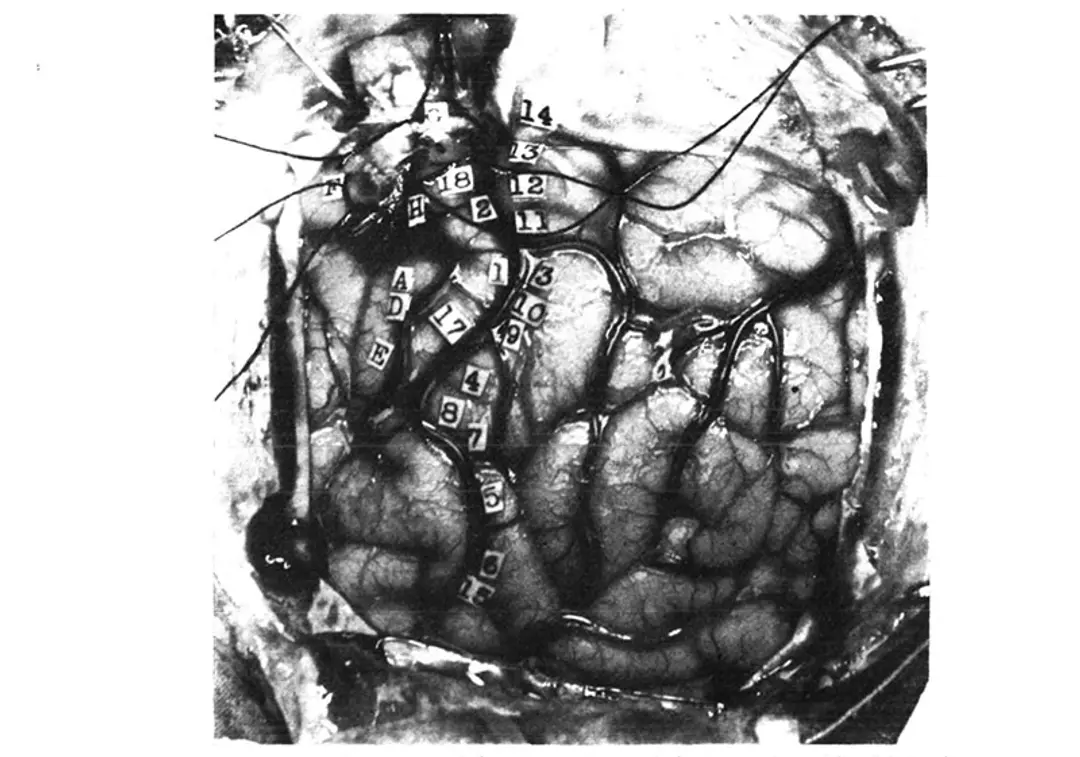

Here, stimulation in front of the fissure evoked small movements or muscle twitches in specific parts of the body, and stimulation just behind it evoked sensations instead. Importantly, the body appeared to be mapped in a highly organised manner in both of these regions, such that stimulation of adjacent patches in either evoked movements or sensations in adjacent body parts on the opposite side of the body. Thus, stimulation of the top of the brain evoked movement or sensation in the hip and torso, and stimulation progressively further down along the outer surface elicited responses first in the shoulder, arm, elbow, forearm, and then the wrist. Finally, there was a large patch of both strips of tissue devoted to the hand, with each finger represented individually, and another large patch devoted to the face, tongue and throat. Crucially, although the precise size and location of the tissue devoted to each body part differed between patients, the sequence of responses elicited by progressive stimulations from the top to the bottom of the brain was always the same. During each procedure, Penfield would place small numbered stickers on the patients brain, and take note of the response evoked by electrical stimulation of that particular patch of tissue (see figure below):

From Wilder Penfield and Edwin Boldreys 1937 paper. American Neurological Association

14. Tingling from the knee down to the right foot, no numbness.

13. Numbness all down the right leg, did not include the foot.

12. Numbness over the wrist, lower border, right side.

11. Numbness in the right shoulder.

3. Numb feeling in hand and forearm up to just above the forearm.

10. Tingling feeling in the fifth or little finger.

9. Tingling in first three fingers.

4. Felt like a shock and numbness in all four fingers but not in the thumb.

8. Felt sensation of movement in the thumb; no evidence of movement could be seen.

7. Same as 8.

5. Numbness in the right side of the tongue.

6. Tingling feeling in the right side of the tongue, more at the tip.

15. Tingling in the tongue, associated with up and down vibratory movements.

16. Numbness, back of tongue, mid-line.

Precentral gyrus from above down:

(G) Flexion of knee.

18. Slight twitching of arm and hand like a shock, and felt as if he wanted to move them.

2. Shrugged shoulders upwards; did not feel like an attack.

(H) Clonic movement of right arm, shoulders, forearm, no movement in trunk.

(A) Extreme flexion of wrist, elbow and hand.

(D) Closure of hand and flexion of his wrist, like an attack.

17. Felt as if he were going to have an attack, flexion of arms and forearms, extension of wrist.

(E) Slight closure of hand; stimulation followed by local flushing of brain; this was repeated with the strength at 24. Flushing was followed by pallor for a few seconds.

(B) Patient states that he could not help closing his right eye but he actually closed both.

(C) Made a little noise; vocalisation. This was repeated twice. Patient says he could not help it. It was associated with movement of the upper and lower lips, equal on the two sides